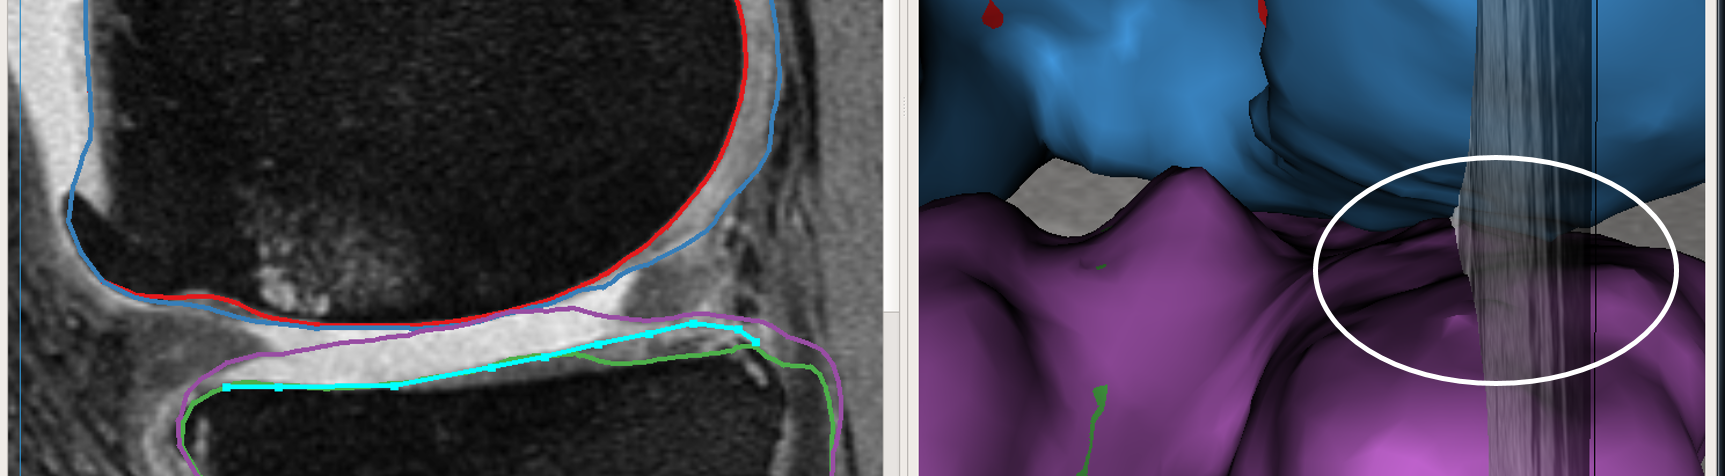

Max-flow re-computation: Following the local graph cost modification the max-flow is recomputed in 3D within a few milliseconds and the updated surfaces rendered onto the GUI. As seen in Fig. 3b the correction made by the nudge points are reflected in the updated cartilage surface overlayed on the image volume.

The above work-flow is repeated to correct the tibial cartilage errors as well. In the intermediate steps following the correction of the femur, the tibia bone and cartilage surfaces appear to worsen. This can be attributed to a combination of the existing graph costs and the graph constraints. Since the tibia cartilage surface has no clear defined edge cost in that region, the surface result moved along with the femur corrected cartilage surface. Subsequently due to the inter-surface distance constraints between the tibial surfaces the tibial bone surface also changed. However once the nudge points provided the appropriate locations for cost modification the erroneous surfaces were corrected (Figs. 3c,d). Note that the corrections made on a single 2D slice resulted in the entire locally affected 3D neighborhood being corrected. This can be appreciated in the corresponding circled regions of the surface model.